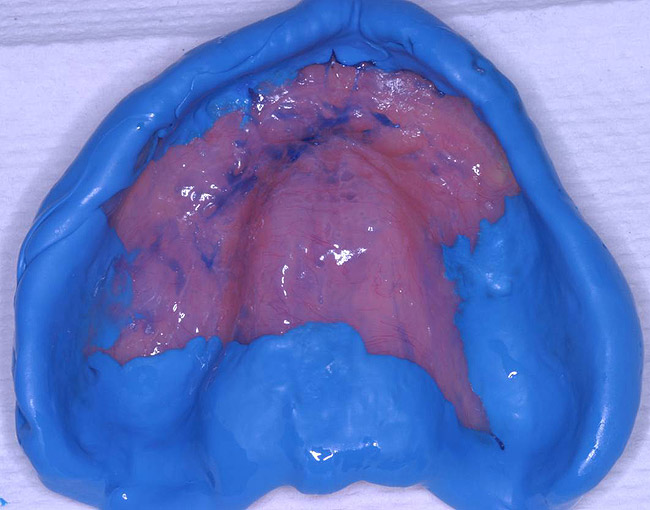

The patient's tissues were freed of excess saliva while the impression material (Take 1 Fast Set Tray Material, Kerr Corporation) was placed on the denture borders chairside (Figure 6). The denture was placed to begin the modified functional impression process and the standard border-molding adjustments to capture the details of the mu cco-buccal folds. After the 4-minute set time recommended by the manufacturer, the denture was removed and the impression was checked for insufficiencies (Figure 7). Once the border mold was deemed acceptable, a low-viscosity impression material (Take 1® Fast Set Wash Material, Kerr Corporation) was extruded onto the palatal area of the denture/tray to finely capture the necessary details of the edentulous mucosa (Figure 8 and Figure 9). A fluid, low-viscosity material is optimal for achieving this result and minimizing unwanted pressure on the maxilla. Again,the standard border-molding techniques were observed to ensure proper integration with the high-viscosity impression material and properly control the impression accuracy. The recommended 4-minute intraoral set-time was observed.

Figure 8  Take 1 Impression material to be used as a wash for the remainder of tissue detail.

Figure 8

Figure 9  Final detailed impression to be immediately poured up.

Figure 9